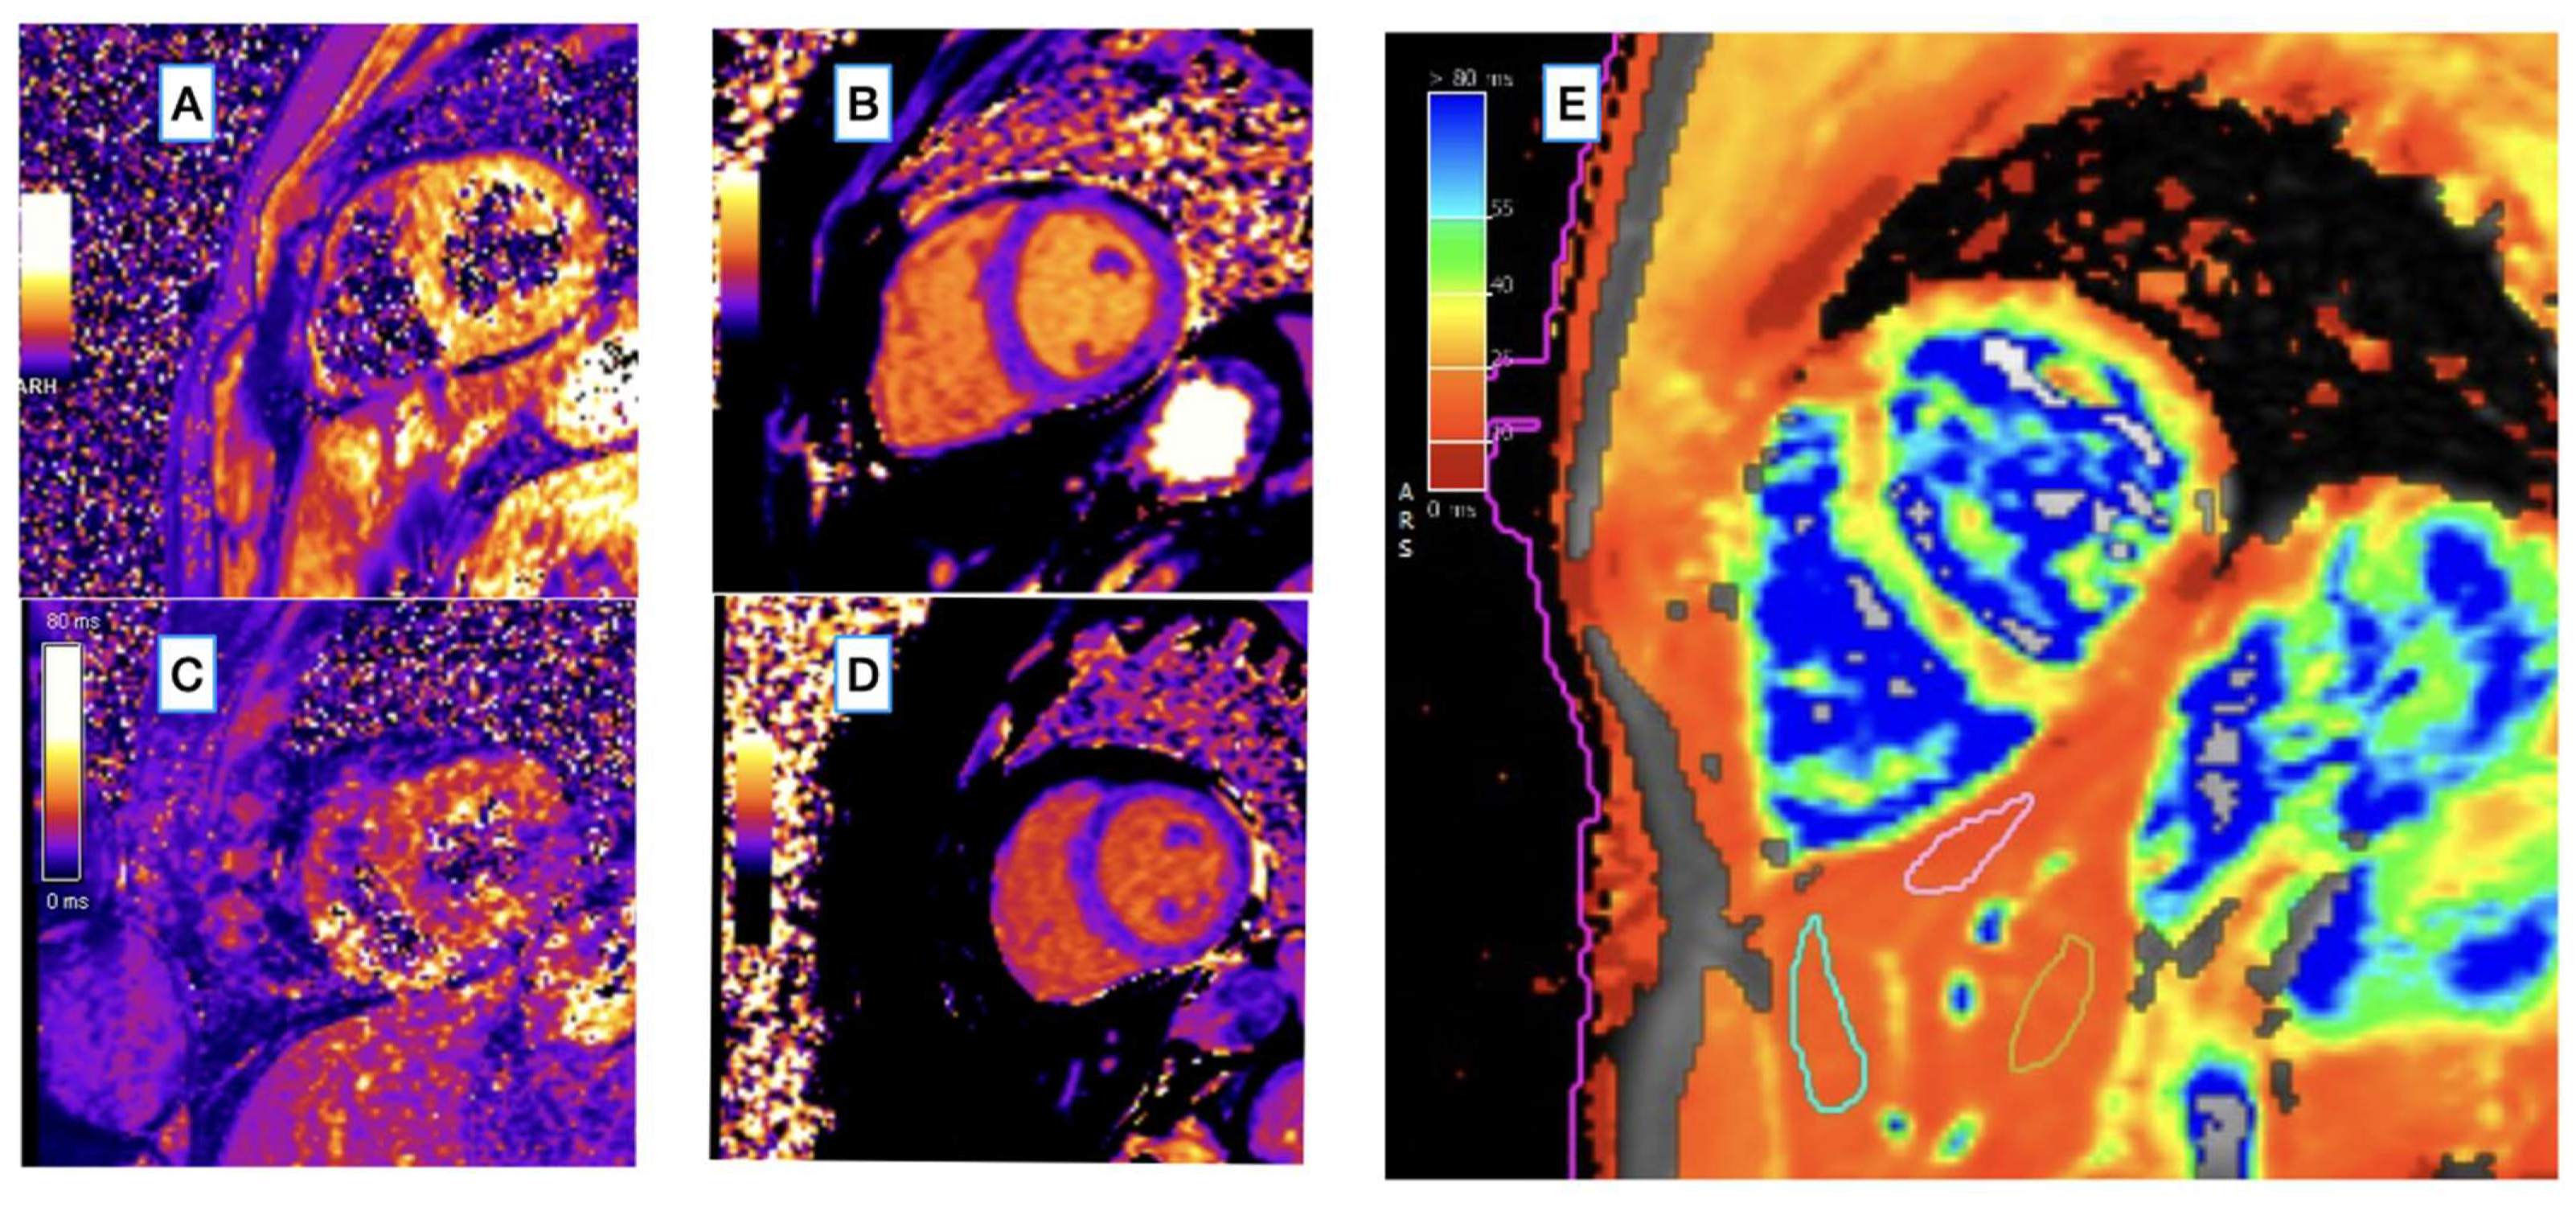

2.2. CMR Image Acquisition

2.3. CMR Image Analysis